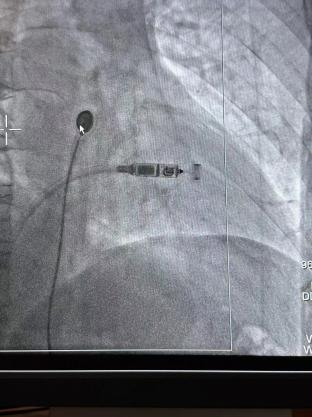

術(shù)前準(zhǔn)備充分后,李大爺在局部麻醉下行無(wú)導(dǎo)線心臟起搏器植入。心血管內(nèi)科醫(yī)生從大爺大腿根部?jī)H穿刺一個(gè)米粒粗細(xì)的小口,通過(guò)導(dǎo)管將起搏器植入心腔內(nèi)。該手術(shù)1個(gè)小時(shí)即順利完成,手術(shù)過(guò)程中大爺完全清醒,幾乎無(wú)疼痛感覺(jué)。

據(jù)悉,Micra無(wú)導(dǎo)線起搏器被稱(chēng)為“全球最小的心臟起搏器”,其體積相比傳統(tǒng)心臟起搏器減小93%,重量約傳統(tǒng)起搏器的1/10。

該術(shù)式經(jīng)穿刺后直接植入在心腔內(nèi),無(wú)需在胸前皮下制作囊袋。無(wú)傷疤、無(wú)切口,患者恢復(fù)時(shí)間快,減少了創(chuàng)傷與感染風(fēng)險(xiǎn),大大改善了患者的生存質(zhì)量。